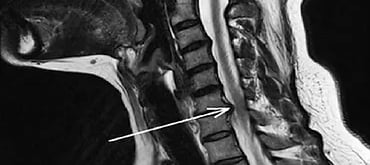

You might have heard the words “herniated disc” or “slipped disk”, a condition when the gel-like fluid in the centre of a spinal disc pushes out through the weak spot in the tough outer wall. Similarly, cervical disc prolapse is the herniation that occurs in the cervical spine.